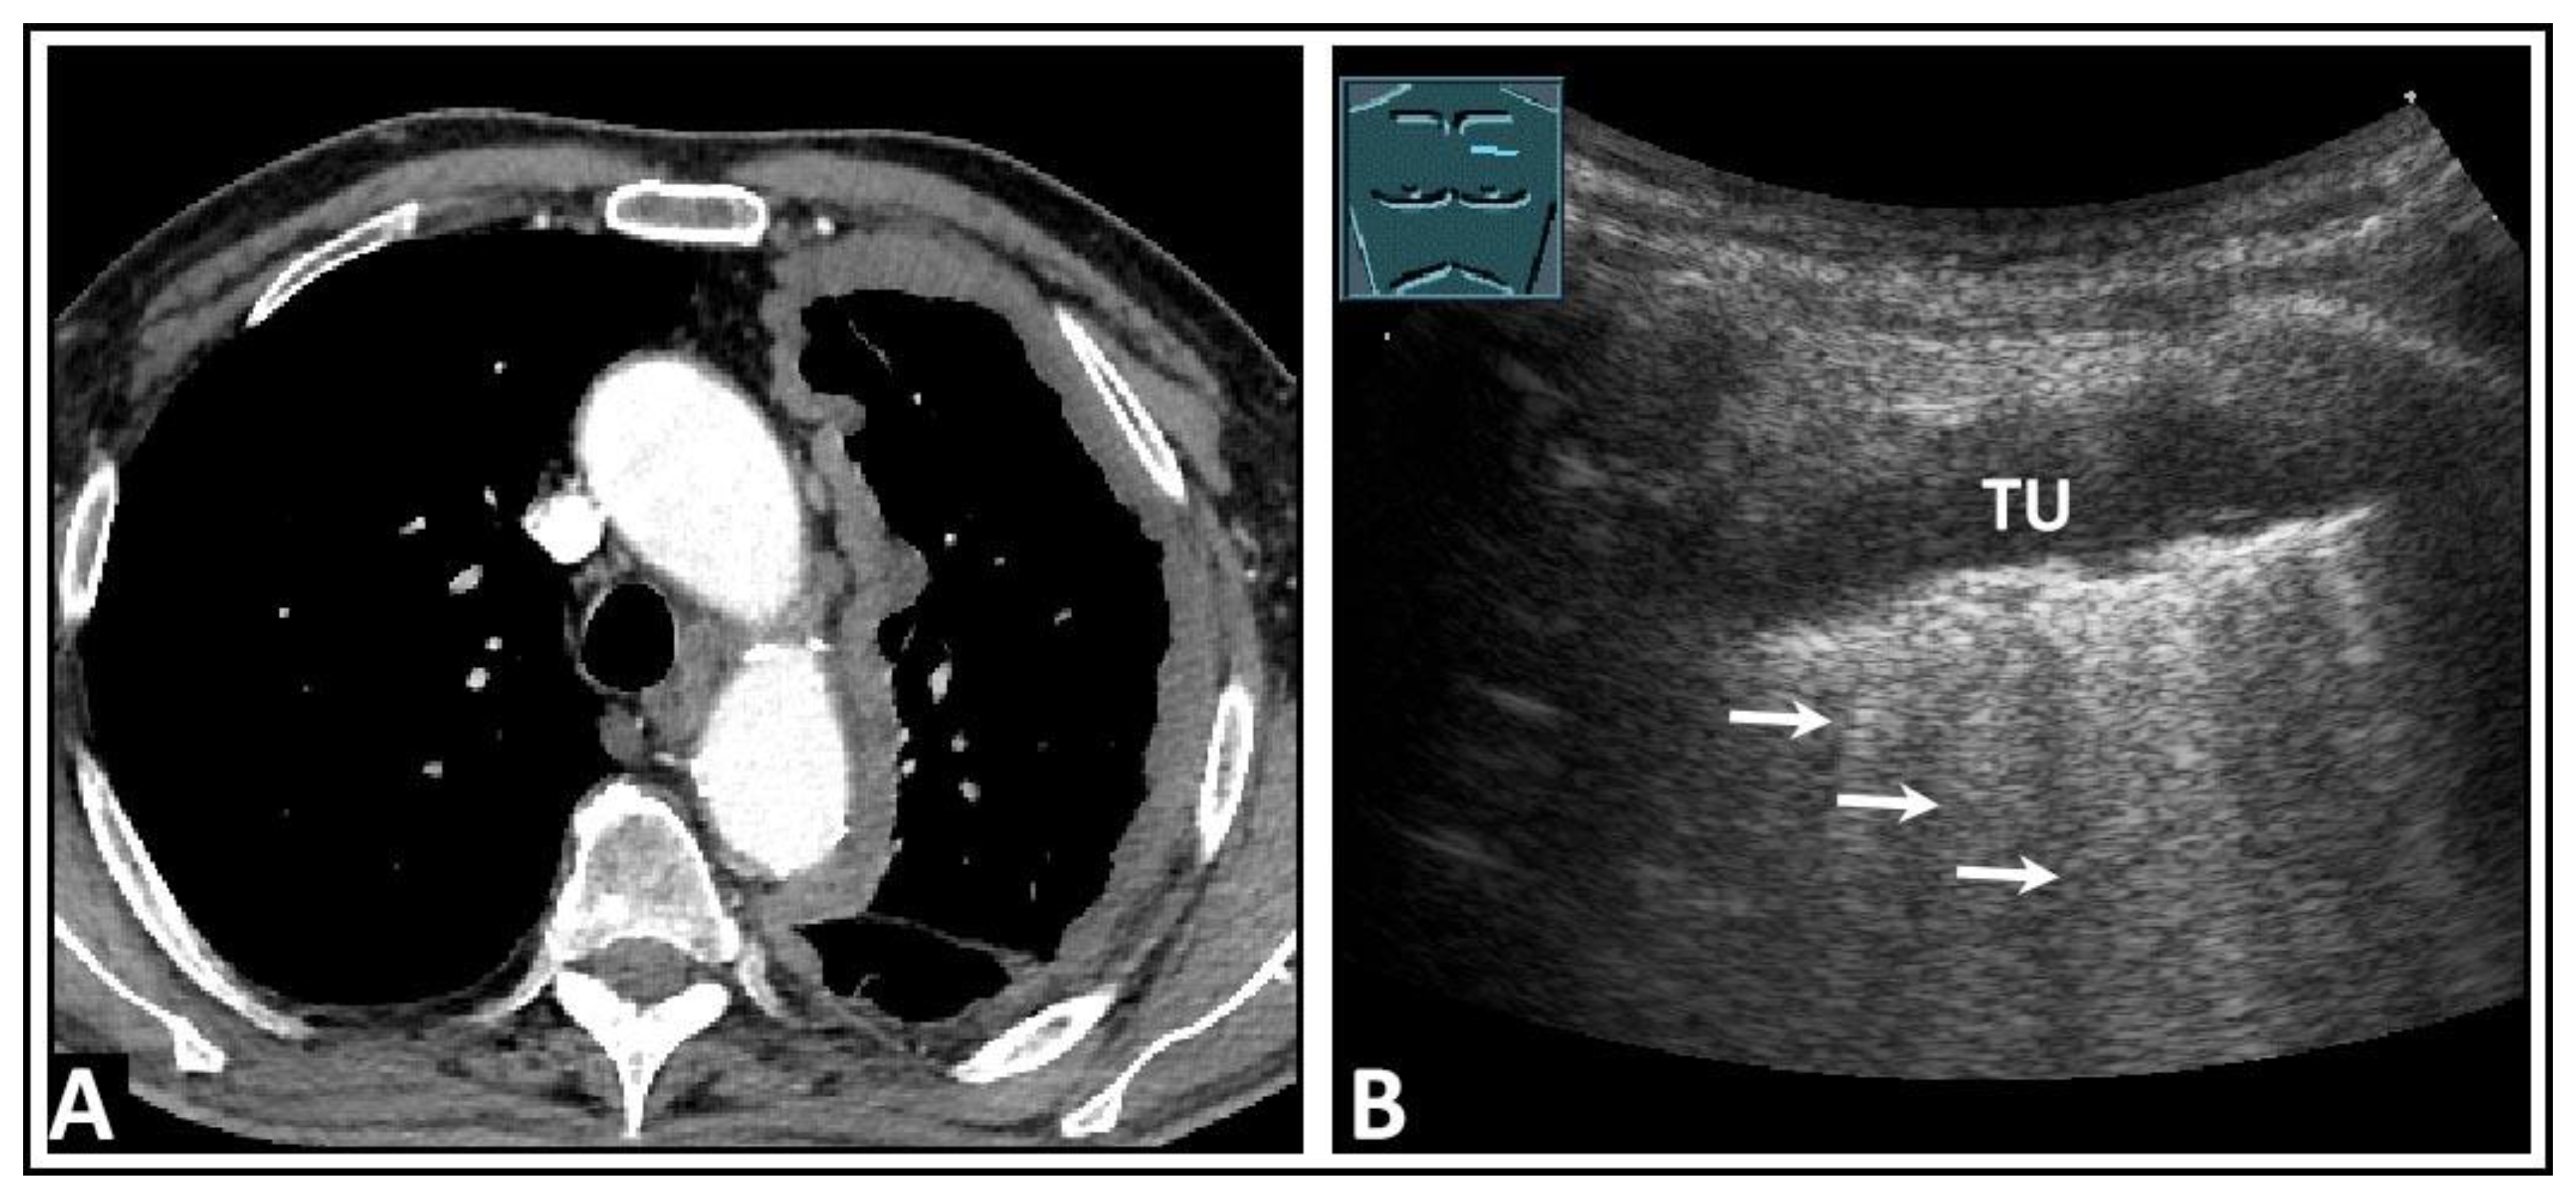

8. Pleural Artifacts with Simultaneous Presence of Consolidation